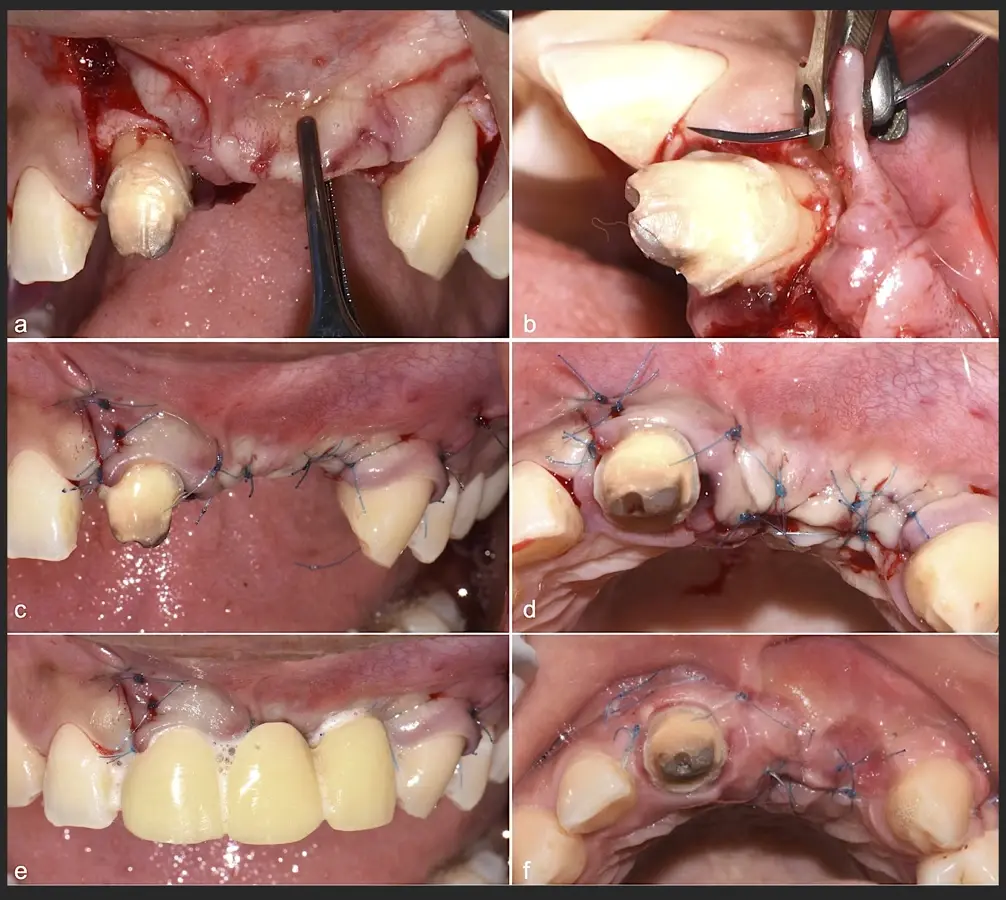

Figura 45. Afrontamiento de colgajo y sutura (a - e). Control a los 7 días postquirúrgico (f).

Figura 46. Control a los 10 días post cirugía.